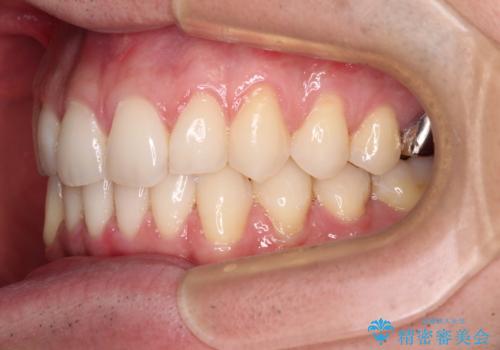

ディープバイトと叢生 インビザラインによる矯正治療

- 前歯のディープバイトと叢生を気にして来院された患者様です。

目立ちにくい装置を希望されていたため、ワイヤー装置とインビザラインを提案したところ、インビザラインを希望されました。

上下ともに叢生が認められたため、親知らずすべてを抜歯し、歯列全体を後方へ移動させることで歯列を整えることとしました。

上顎奥歯の銀歯も気になっていたので、矯正治療の途中でセラミッククラウンへ変更し、その後歯列を仕上げていくこととしました。

ディープバイトもデコボコも改善され、気になっていた銀歯もセラミックとなり、患者様には大変満足していただきました。